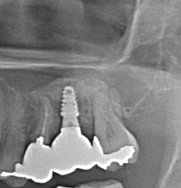

下顎管まで近いケースショートインプラントと垂直GBR(骨造成)で対応した →インプラント埋入

治療前

治療後

施術名 | インプラント埋入垂直GBR(骨造成) |

主訴 | 噛めない |

施術の副作用(リスク) | 感染脱落 |

施術の価格 | 1本GBR5万~10万(税抜き)+インプラント埋入補綴まで35万(税抜き) FGG5万 |

コメント | 下顎管まで近いケースショートインプラントと垂直GBR(骨造成)を同時に行いました |